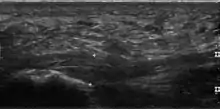

Plantar fasciitis is usually diagnosed by a health care provider after consideration of a person's presenting history, risk factors, and clinical examination.[4][17][18] Palpation along the inner aspect of the heel bone on the sole may elicit tenderness during the physical examination.[4][11] The foot may have limited dorsiflexion due to excessive tightness of the calf muscles or the Achilles tendon.[7] Dorsiflexion of the foot may elicit the pain due to stretching of the plantar fascia with this motion.[4][12] Diagnostic imaging studies are not usually needed to diagnose plantar fasciitis.[7] Occasionally, a physician may decide imaging studies (such as X-rays, diagnostic ultrasound, or MRI) are warranted to rule out serious causes of foot pain.

The plantar fascia has three fascicles-the central fascicle being the thickest at 4 mm, the lateral fascicle at 2 mm, and the medial less than a millimeter thick.[19] In theory, plantar fasciitis becomes more likely as the plantar fascia's thickness at the calcaneal insertion increases. A thickness of more than 4.5 mm ultrasound and 4 mm on MRI are useful for diagnosis.[20] Other imaging findings, such as thickening of the plantar aponeurosis, are nonspecific and have limited usefulness in diagnosing plantar fasciitis.[13]

Three-phase bone scan is a sensitive modality to detect active plantar fasciitis. Furthermore, a 3-phase bone scan can be used to monitor response to therapy, as demonstrated by decreased uptake after corticosteroid injections.[21]